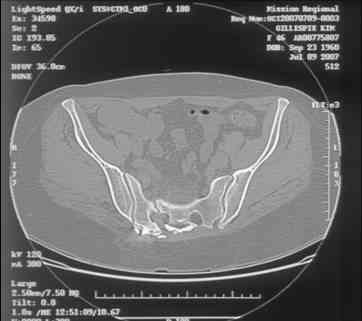

Re: Sacral Non-Union

Chip Routt 23 Август 2007, 23:06

Maybe remove the disengaged iliosacral screw first to see if she improves?

I can't see the axial CT images well enough to detail the potential sacral issues....can you magnify them?

David Zamorano 25 Август 2007, 21:05

Here is a magnified view. Sorry about the quality but the CT was scanned into our system.

dave